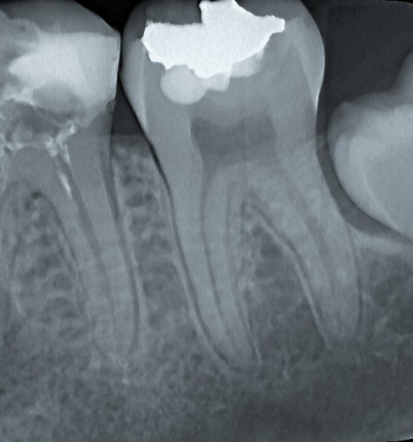

- parodontalno ter endodontsko zdravljenje,

Redni pregledi omogočajo zgodnje odkrivanje kariesa, bolezni dlesni in drugih težav, še preden povzročijo bolečino ali zahtevnejše posege. S pravočasnim ukrepanjem lahko ohranimo več zdrave zobne strukture, zmanjšamo stroške zdravljenja ter dolgoročno poskrbimo za boljše ustno in splošno zdravje. Naša dobra zobozdravstvena ordinacija (Slovenija) z veseljem poskrbi tako za preventivo kot za zdravljenje že nastalih bolezni. Kontaktirajte nas za pregled oziroma za posvetovanje.